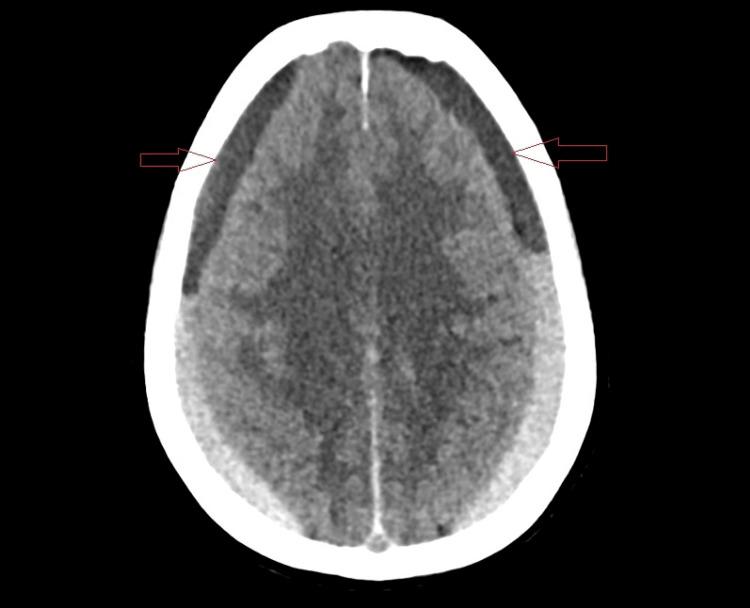

The delayed onset of posttraumatic subdural hemorrhage (SDH) represents non-specific clinical features, complicating the diagnostic process, especially in individuals predisposed due to pre-existing risk factors and comorbidities. This case report delineates the medical trajectory of a 61-year-old female patient who sustained a traumatic fall, initially displaying neither clinical nor radiological signs indicative of hemorrhage. However, three weeks post-injury, she developed altered mental status, cephalgia, and emesis. Diagnostic imaging unveiled a significant bilateral acute-on-chronic subdural hemorrhage exerting pronounced mass effect and leading to obliteration of the basal cisterns. Complicating her clinical picture was a concurrent SARS-CoV-2 infection and a medical history of hypertension. Emergent neurosurgical intervention was undertaken, encompassing the creation of bilateral burr holes for drainage and the placement of subdural drains. The patient was managed with the requisite medical therapies. Post-operatively, the patient regained consciousness and exhibited significant neurological improvement. Follow-up imaging demonstrated complete resolution of the subdural hemorrhage, and the patient achieved a full recovery of cognitive function. This case underscores the critical necessity for vigilant surveillance for delayed SDH in patients lacking initial radiographic findings and advocates for individualized therapeutic approaches in patients with concurrent pathologies. Prompt recognition, timely neurosurgical management, and care are pivotal to optimizing outcomes in delayed posttraumatic SDH cases.

创伤后硬膜下血肿(SDH)的延迟发生表现出非特异性临床特征,使诊断过程复杂化,尤其是在因既有危险因素和合并症而 predisposed 的个体中。本病例报告描述了一名61岁女性患者的医疗轨迹,该患者因创伤性跌倒入院,最初既无临床症状也无影像学迹象表明有出血。然而,受伤三周后,她出现了精神状态改变、头痛和呕吐。诊断性影像学检查发现双侧有明显的急性-on-慢性硬膜下血肿,产生了明显的占位效应并导致基底池闭塞。使她的临床情况复杂化的是同时感染了SARS-CoV-2以及有高血压病史。进行了紧急神经外科干预,包括双侧钻孔引流和放置硬膜下引流管。患者接受了必要的药物治疗。术后,患者恢复了意识并在神经功能方面有显著改善。随访影像学检查显示硬膜下血肿完全消退,患者认知功能完全恢复。本病例强调了对缺乏初始影像学表现的患者进行警惕性监测以发现延迟性SDH的至关重要性,并提倡对合并多种病症的患者采取个体化治疗方法。及时识别、及时的神经外科处理和护理对于优化创伤后延迟性SDH病例的治疗结果至关重要。